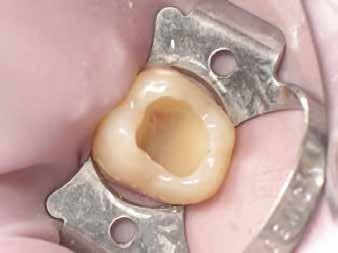

2. ábra: A páciens egy nem megfelelő I. osztályú ezüstamalgám töméssel és II. osztályú szuvasodással jelentkezett. A fog izolálása kofferdám alkalmazásával történt.

3. ábra: A preparálás, a bondozás és a kompozit felvitele után. (Megjegyzés: némi kompozit túlfolyás látható a mesiális doboz axiális falain).

4. ábra: A durva finírozás után a restauráció pereme sima és anatómiailag is megfelelő.